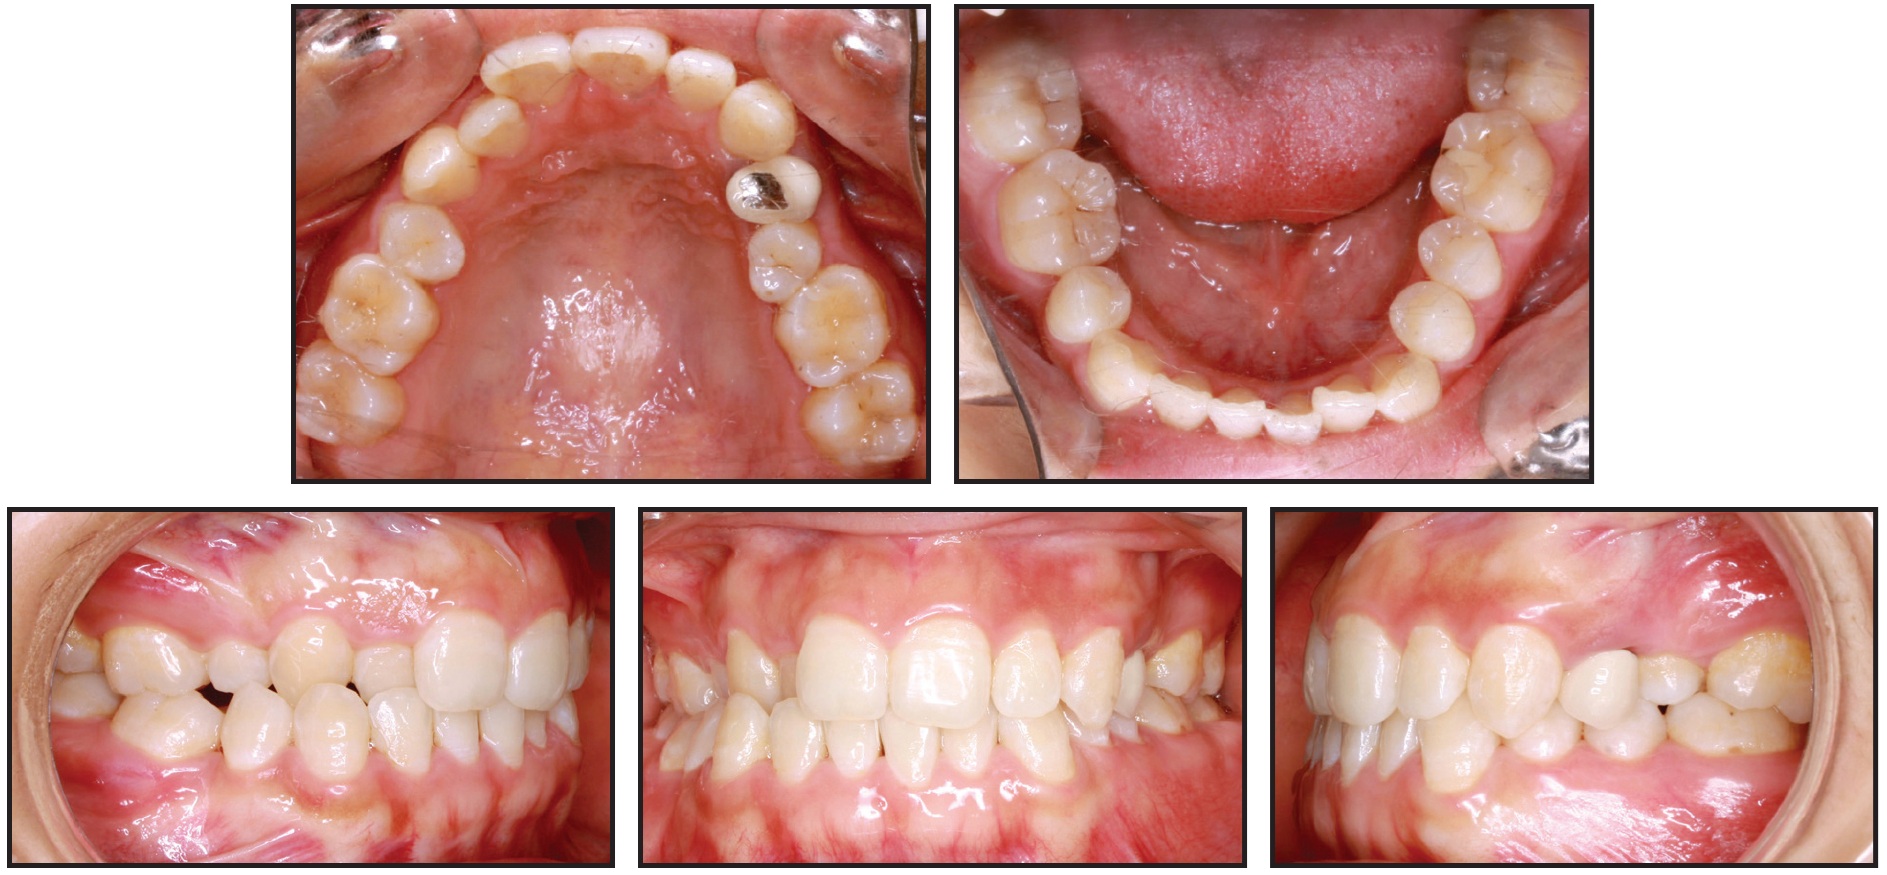

The procedure is illustrated in a 32-year-old female who presented with a skeletal and dental Class I malocclusion (Fig. 1).

Fig. 1 32-year-old female Class I patient with missing upper right first and lower right second premolars before treatment.